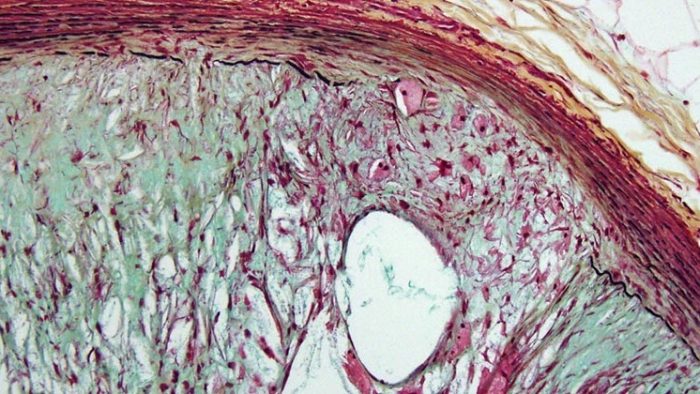

As a vital part of the Institute’s overall cardiovascular research team, THI’s cardiovascular pathologists work to provide researchers with critical information they need to progress their studies forward.